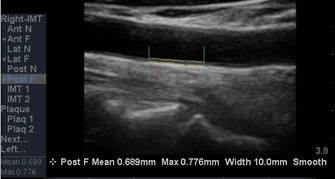

The CIMT procedure is

simple. An ultrasound study is carried out of the carotid arteries in your

neck. A specialized software program is used to precisely measure the mean and

maximum IMT. Standard carotid ultrasound is looking for “flow-limiting”

stenoses, narrowings that could be addressed surgically. This is not what we

are interested in with CIMT testing - we will be measuring soft plaque

accumulation in non-overtly diseased vessel segments (if plaque is identified we

measure the CIMT at an adjacent, normal appearing segment). While the presence

of plaque obviously has significance, it is the IMT parameter that best predicts

the presence and severity of atherosclerotic vascular disease elsewhere in your

body, it’s risk of progression, and your risk of sustaining an atherosclerotic

event (think of IMT as the “staging ground” for obstructive plaque – the higher

the IMT, the greater the rate of IMT progression, the more rapidly will large,

obstructive plaques form). Over 2,000 studies (go to www.pubmed.gov and enter

Carotid IMT) document the link between CIMT and current risk, and an even more

powerful relationship between the rate of change in CIMT and future risk. We

will use CIMT to help us decide who should be treated with preventive measures

and how aggressive our efforts should be. We will use the rate of change of

CIMT to gauge the success of the regimens that we construct for you.